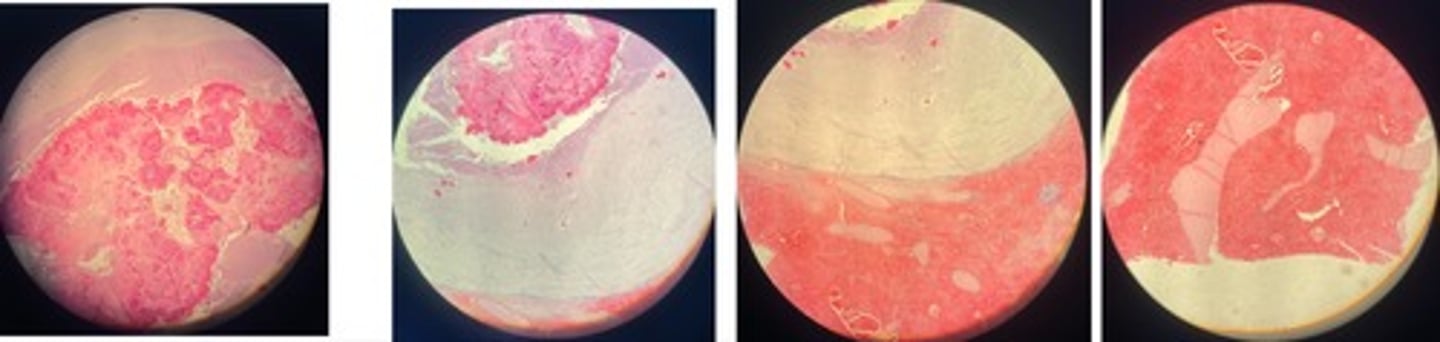

Organisation of fibrin during post-traumatic pericarditis

- heart is covered in fibrin w/ vilious like projections

- young + old granulation tissue

- fat, inflam cells, myocardium

Chronic interstitial nephritis

- inflam (lymphocytes, plasma cells, macrophages) infiltrates in interstitial tissue

- hyperplasia of fibrous tissue

- retention cysts in lower parts of tubules

- atrophy of renal tubules